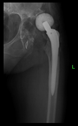

The radiological examination allowed us to verify the close bone-to-implant contact and the unchanged position of the implant during follow-up.

In all the cases operated with the above-described targeting procedure, the stems of the cups remained between the cortical bone surfaces without perforation of the linea terminalis, as shown by postoperative radiographs. There were no complicated surgical situations. In 16 cases, the wound healings were uneventful, and the hips were able to bear weight again after postoperative rehabilitation.

The only patient who suffered an infection healed after the removal of the implant. This complication rate is known and in line with accepted values.

One septic complication occurred. This complication rate is consistent with other revision techniques. In this case, the implant had to be removed, and the patient remained in Girdlestone condition. In such cases, removal of the implants and, of course, surgical debridement and antibiotic treatment are essential. The condition after resection is called Girdlestone’s condition. We had no other complications or unexpected outcomes.